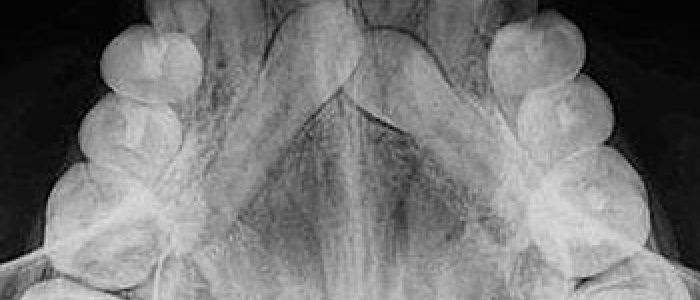

Son aquellas en las que la película se coloca en el interior de la cavidad bucal. Según el tamaño y la colocación de la película se pueden clasificar en procedimientos periapicales o retroalveolares o retroalveolares, bite wing o interproximales y oclusales.